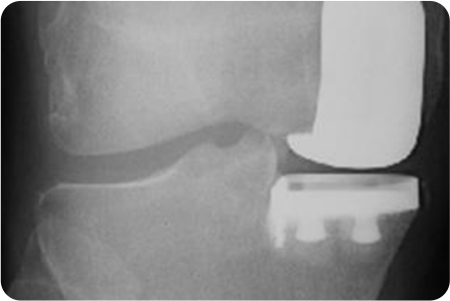

부분치환술

부분치환술 관련 이미지

• 무릎 내측에만 관절염이 있는 경우

• 전방십자인대의 기능이 살아있는 경우

• 다리변형이 10도 이내인 경우

• 다리 구부리고 펴는 것이 일정각도 이상 가능한 경우